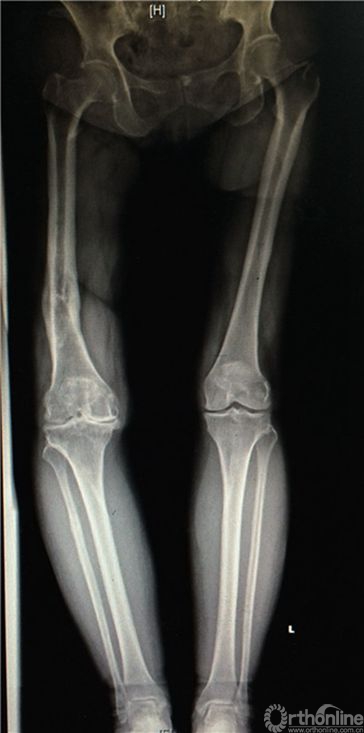

患者女性,69岁,病史7年。表现为逐渐加重的右膝关节疼痛、活动受限,负重行走和劳累后出现,上下楼梯更重,初始休息后可缓解,经口服硫酸氨基葡萄糖,非甾体类消炎药物,及“小针刀”,关节内注射玻璃酸钠等多种保守治疗,3年前疼痛、活动受限明显加重,影响日常生活就诊。23年前车祸伤致右股骨中下段粉碎骨折,外院行切开复位内固定,术后7月内固定松动,骨折未愈合,遂再次行切开复位内固定,髂骨取骨植骨术,直至骨折愈合后1年取出内固定。有高血压病史,规律服用降压药物控制良好。患者身高153cm,体重85公斤,BMI36kg/m2。右膝外上25cm术后瘢痕,右膝活动度10-90度,膝内外侧均有压疼,髌磨阳性。术前全长X片,膝关节负重正侧位片提示右膝关节重度骨性关节炎,右股骨中下段成角畸形(图1a,1b,1c)。

图1a. 双下肢全长片,右膝重度骨性关节炎,右股骨中下1/3陈旧骨折畸形愈合,向内侧成角畸形。

图1b. 右股骨中下段内侧成角畸形,股骨外翻角约14度。

图1c. 矢状位显示股骨中下段无明显成角畸形。